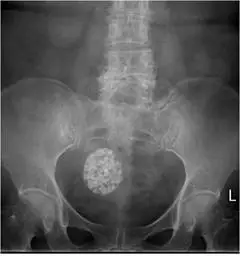

一位 65 歲女性病患,無症狀。腹部 X光片意外發現一個高度鈣化的陰影(如上圖)。 超音波檢查如下圖。其診斷為何:

圖一(腹部 X 光): 骨盆腔中央可見一個邊界清楚的圓形高密度鈣化腫塊,呈現散在分布的「爆米花狀(popcorn-like)」緻密鈣化灶,整體鈣化程度相當高。腫塊位於骨盆正中央偏下,位置符合子宮。此影像特徵為典型退化性鈣化(dystrophic calcification)子宮肌瘤。